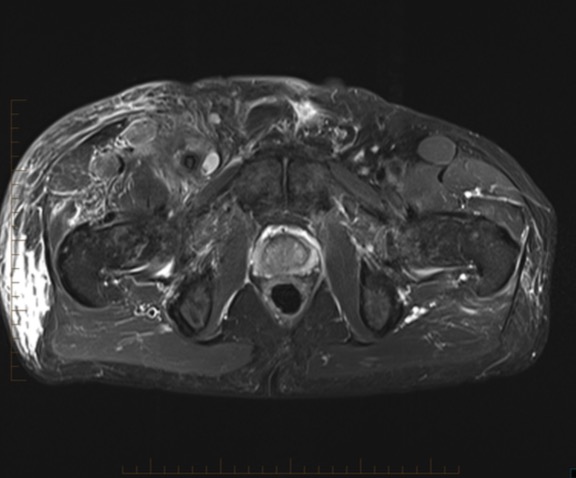

70 male prostate CA with groin mass

FEMORAL ARTERY LEIOMYOSARCOMA WITH BONE METASTASES.